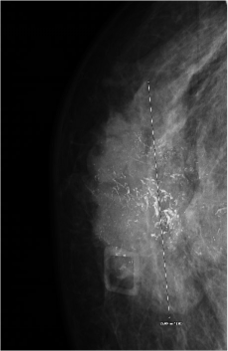

Following her presentation in clinic, a mammogram and magnetic resonance imaging were performed and showed a 4.7 × 1.8 × 5.0-cm subareolar mass extending to the nipple areolar complex and skin that involved all 4 quadrants of the breast but did not demonstrate any extension of the mass to the pectoralis muscle (Figure 1). The patient and her physicians agreed on pursuing both surgical treatment and chemotherapy. The patient initially underwent a right skin-sparing mastectomy with right targeted sentinel lymph node biopsy and immediate right breast reconstruction with a tissue expander. The histopathology report demonstrated a biopsy-proven metastatic right lymph node, and the patient was diagnosed with stage 3 invasive ductal carcinoma. Immunohistochemistry demonstrated triple-positive receptors: estrogen receptor positive (ER+), progesterone receptor positive (PR+), and human epidermal growth factor receptor 2 positive (HER2+). Genetic testing revealed a variant of uncertain significance in PALB2 (c.866T>C; p.Leu289Ser), the partner and localizer of BRCA2.

Figure 1. Irregular right breast findings. The image shows a highly suspicious irregular spiculated heterogenous hypoechoic mass with multiple microcalcifications that extends to the skin surface. This mass is approximately 4.7 × 1.8 × 5.0 cm.